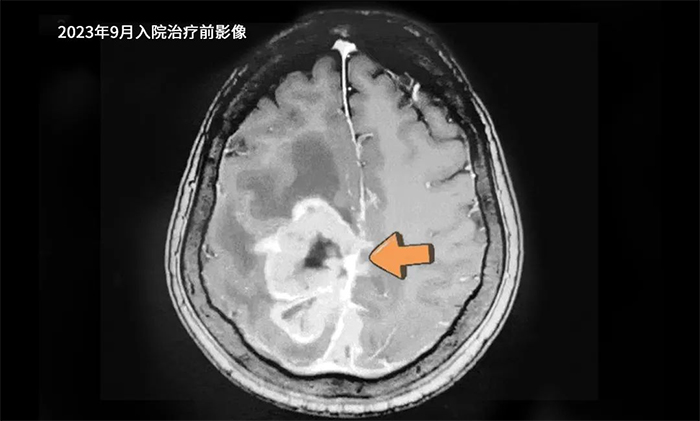

患者赵某(化名),女性,73岁。2014年因右肺肿瘤至当地医院行手术切除,术后恢复良好。2023年7月,因发现脑转移占位病变,于外院行开颅手术,病理报告为转移性神经内分泌癌。术后,左侧肢体活动障碍逐渐加重,9月复查头颅增强核磁共振提示肿瘤复发。遂来我院对颅内肿瘤病灶进行进一步治疗。

▲ 入院治疗前影像

入院时查体,受肿瘤占位效应影响,患者左侧肢体肌力0级,无法自己行走,需要借助轮椅,生活自理能力大受影响。经肿瘤科(放疗)头部伽玛刀组陈琦主任精心治疗,病情明显控制。